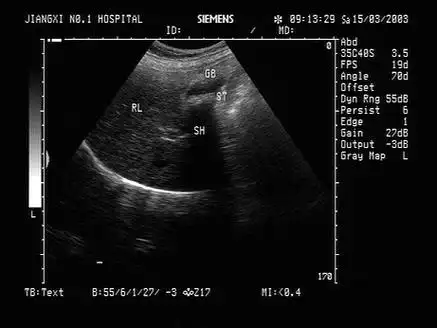

胆囊泥沙样结石